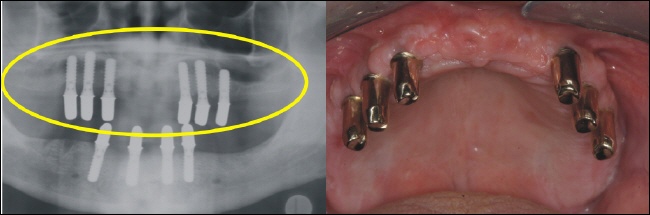

Die fertige Arbeit ermöglicht auf den sechs Teleskopen im Oberkiefer eine rein kieferkammbegrenzte, also gaumenfreie Versorgung. Das Röntgenbild links zeigt die solide Konstruktion, die eine reine Kaukraftweiterleitung in den Kieferknochen ermöglicht. |

Auch im Unterkiefer ist der Zahnersatz auf den Kieferkamm begrenzt und ermöglicht so höchsten Tragekomfort. |

Ein zufriedener Patient mit einem erheblichen Gewinn an Lebensqualität ist sicher versorgt und bissfest hoffentlich sein Leben lang. |